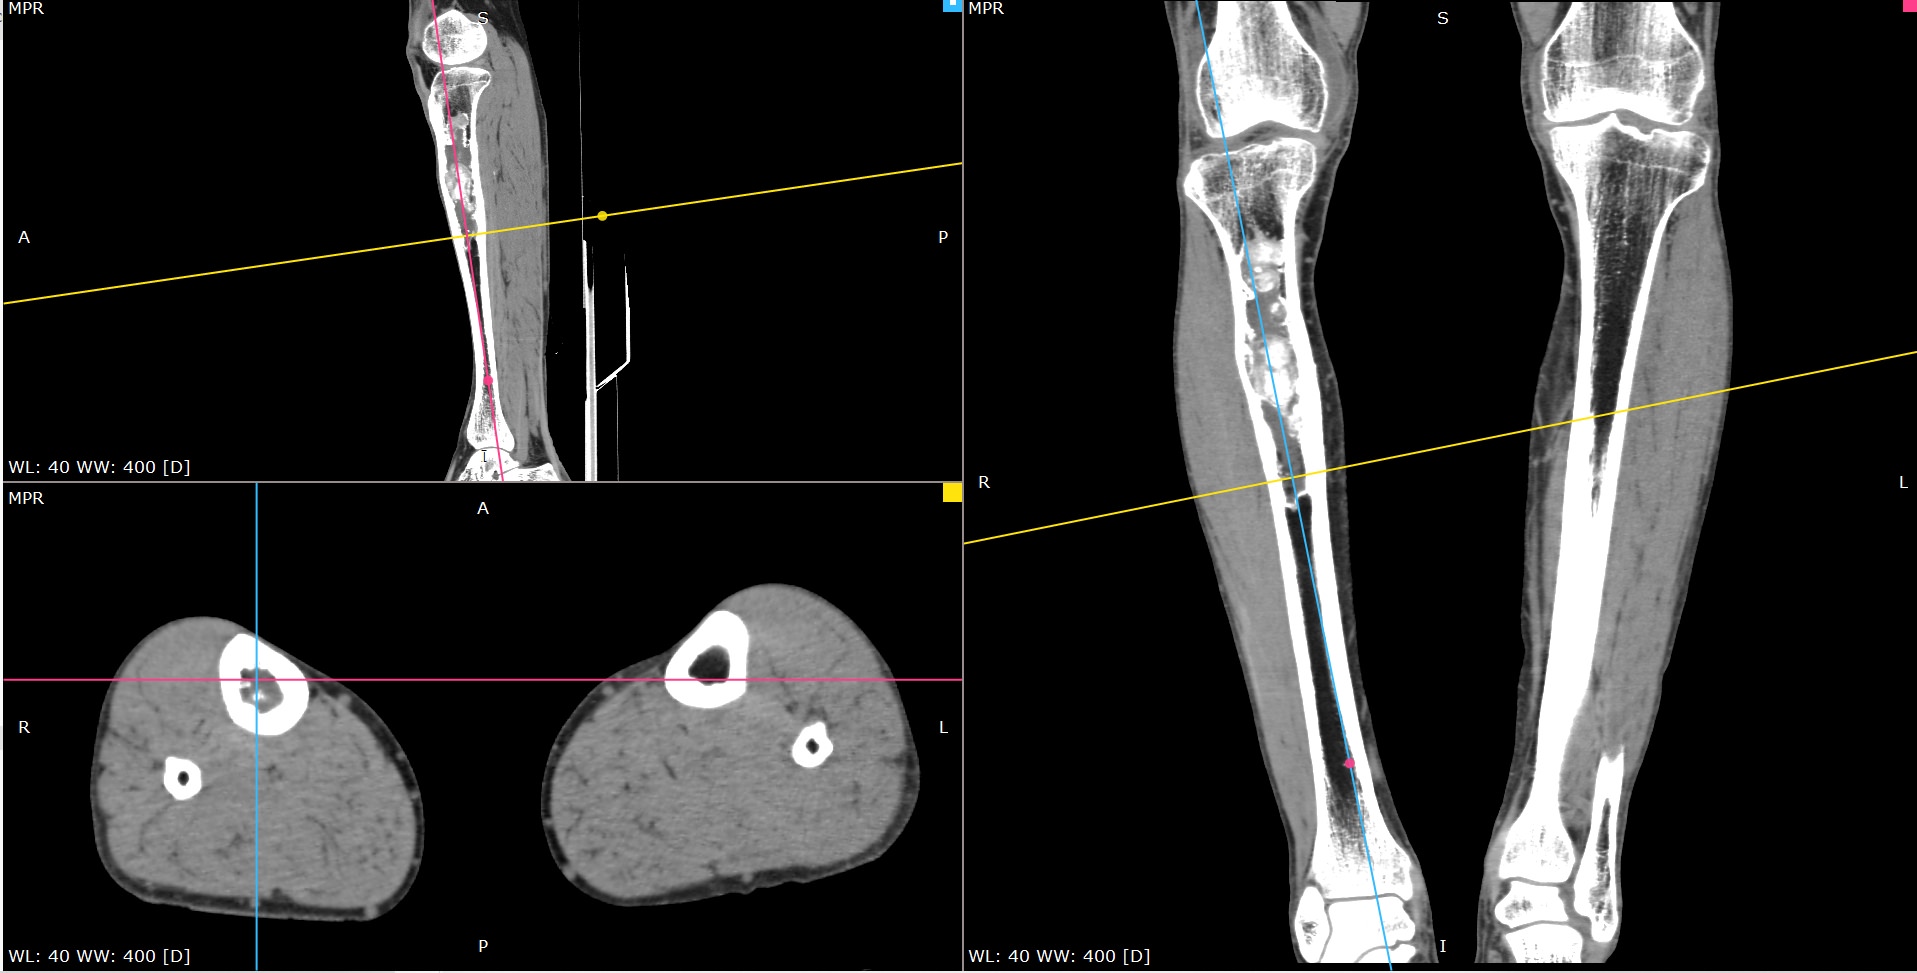

Мультиспиральная компьютерная томография является современным лучевым методом исследования, который позволяет с помощью рентгеновского излучения получить посрезовые снимки и после цифровой обработки создать объемные модели исследуемой области в мельчайших подробностях. Рентгеновские лучи в большей степени поглощаются плотными тканями организма, поэтому на снимках хорошо визуализируются кости скелета. Для более детальной оценки состояния мягкотканных структур зачастую проводится контрастное усиление.

В наших медицинских центрах КТ мягких тканей конечностей выполняется на современных мультиспиральных компьютерных томографах экспертного уровня TOSHIBA AQUILION. Аппараты послойно сканируют область исследования, одномоментно выполняя множество тончайших срезов. В результате получаются снимки высокого качества и трехмерные модели с изображением костного скелета и мягких тканей конечностей. При этом методика скоростного мультисрезового сканирования обеспечивает минимальную дозу рентгеновского облучения для пациента.